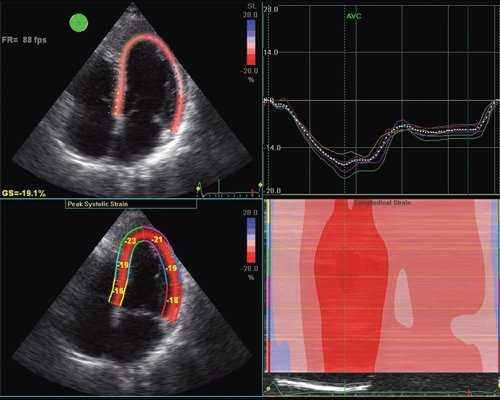

В настоящее время бурное развитие современных ультразвуковых технологий привело к появлению совершенно иных подходов к оценке функционального состояния сердца, которые на очень ранних этапах заболевания позволяют выявлять минимальные нарушения функции сердца. Мы еще не успели должным образом изучить возможности тканевой допплерографии, как появилась еще одна методика, получившая в англоязычной литературе название - speckle tracking. В отличие от тканевой допплерографии, основанной на эффекте допплера, speckle tracking основан на определении скорости движения миокарда при помощи отслеживания перемещения естественных акустических маркеров - пятнистых структур, на стандартном эхокардиографическом изображении в В-режиме (рис. 1).

Суть метода заключается в том, что акустические маркеры случайным образом равномерно распределяются по всему миокарду. Размер каждого пятна составляет от 20 до 40 пикселей (точек). Положение каждого пятна определяется и точно прослеживается на последовательных кадрах. Таким образом, можно определить расстояние, на которое перемещается пятно от кадра к кадру. Зная частоту смены кадров, можно определить скорость движения пятна. С целью повышения качества отслеживания пятнистых структур применяется высокая частота смены кадров - 60-100 кадров в секунду. Особенности движения сердца, вращение в грудной клетке, а также дыхательная экскурсия грудной клетки могут приводить к смещению пятен из плоскости сканирования. Однако эти изменения не успевают произойти в значимом количестве между двумя последовательными кадрами. Таким образом, по движению пятнистых структур можно получить данные о скорости, деформации и скорости деформации всех участков миокарда. Техника вычисления деформации по двухмерному изображению значительно проще, чем при использовании тканевой допплерографии, так как при этом отсутствуют ограничения, связанные с параллельностью движения объекта и ультразвукового луча. Для последующих вычислений достаточно одного сердечного цикла (рис. 2). Обработка ультразвуковых изображений проводится в режиме offline [2].

![Эхограмма (В-режим) - оценка продольной деформации левого желудочка, технология speckle tracking]()

Рис. 2. Оценка продольной деформации левого желудочка с помощью ультразвуковой технологии speckle tracking в В-режиме.

С появлением ультразвуковой технологии speckle tracking стало возможным более детальное изучение регионарной систолической и диастолической функции не только продольных волокон, но и радиальных, окружностных, поскольку, новая технология лишена угловых ограничений, присущих тканевой допплерографии. Это делает возможным исследование продольной сократимости даже верхушечных сегментов левого желудочка. Благодаря технологии speckle tracking стало возможным изучение показателей апикальной и базальной ротации, скручивания и раскручивания сердца, что позволяет по-новому оценивать физиологию сокращения и расслабления миокарда.

Использование технологии speckle tracking при артериальной гипертензии полностью подтвердило нарушение при нормальной фракции выброса продольной систолической функции левого желудочка.